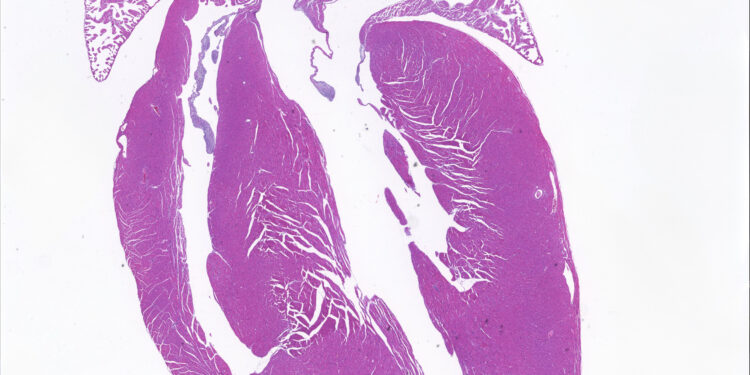

The researchers used a technique called base editing to correct a mutation in the lamin A gene. At 8 months of age, the heart cross-sections of the treated mice resembled those of normal, healthy mice. Credit: Xurde Caravia

To see if their treatment would work in a living body, the team created mouse models with the same LMNA mutations and delivered the base editors using a harmless virus that targets heart and muscle cells. For mice with heart disease caused by the R249Q mutation, the base editors improved heart function and extended their lives by about 80%. For mice with heart disease caused by the L35P mutation, base editing prevented the development of heart disease.